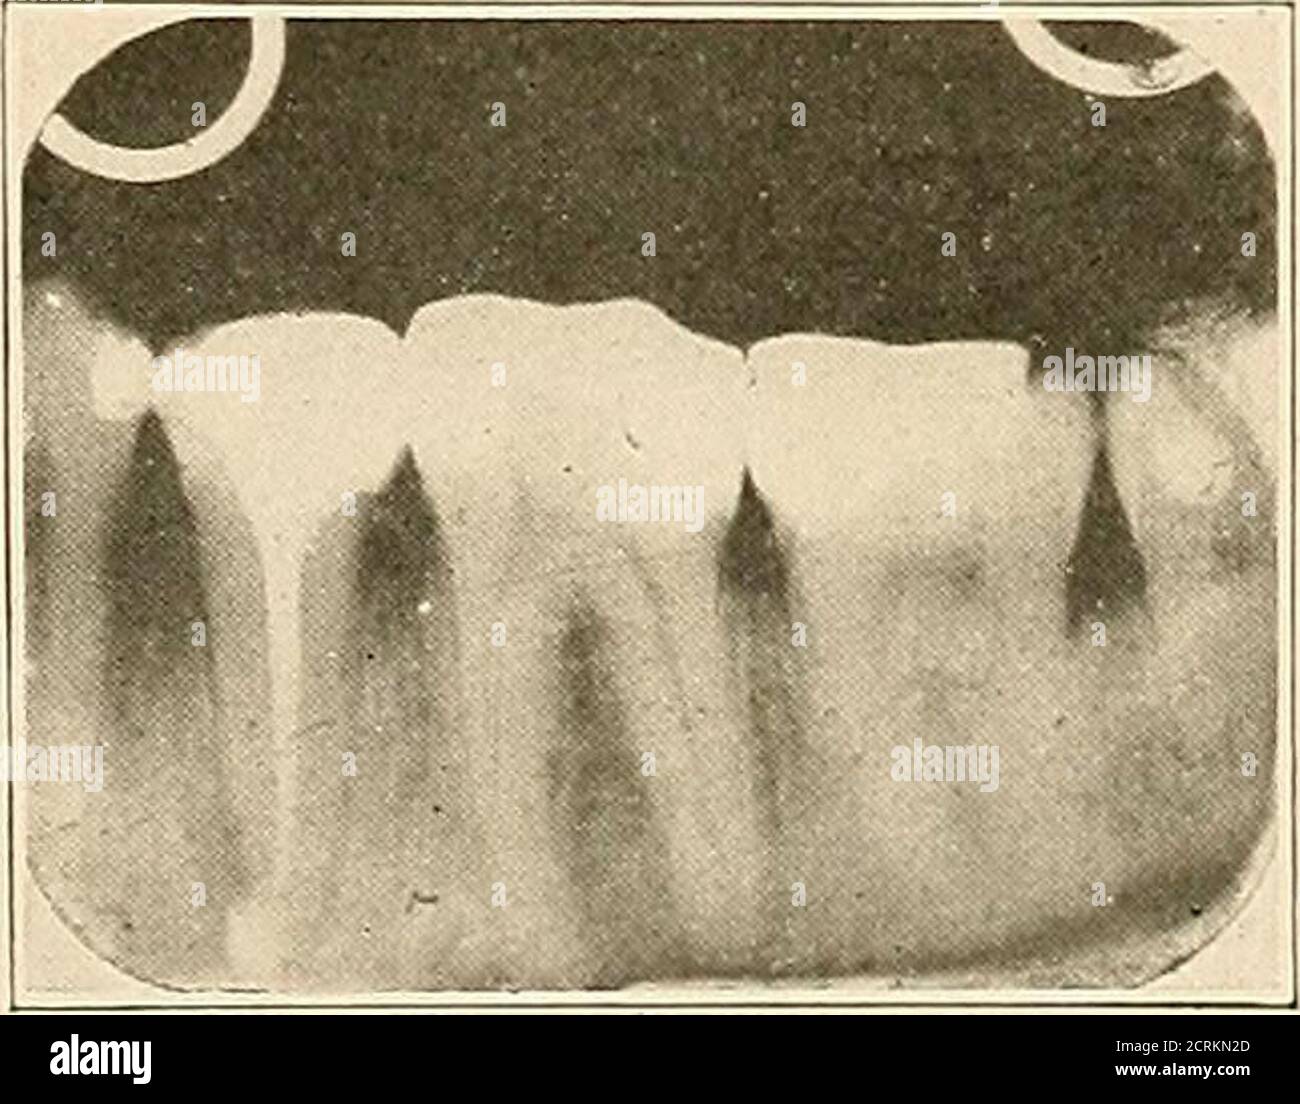

Preclinical radiograph of lower premolars shows the existence of more

. Interpretation of dental & maxillary roentgenograms . Fig. 211.—A Premolar Root Canal X Ray The aim of this study is to investigate root anatomy and root canal morphology of human mandibular first. Mandibular first premolars are familiar with their varied root canal morphology, causing difficulties and challenges for. At least two radiographs, the second from 15° to 20° either mesial or distal from the horizontal long axis of the root, are needed to. The. Premolar Root Canal X Ray.